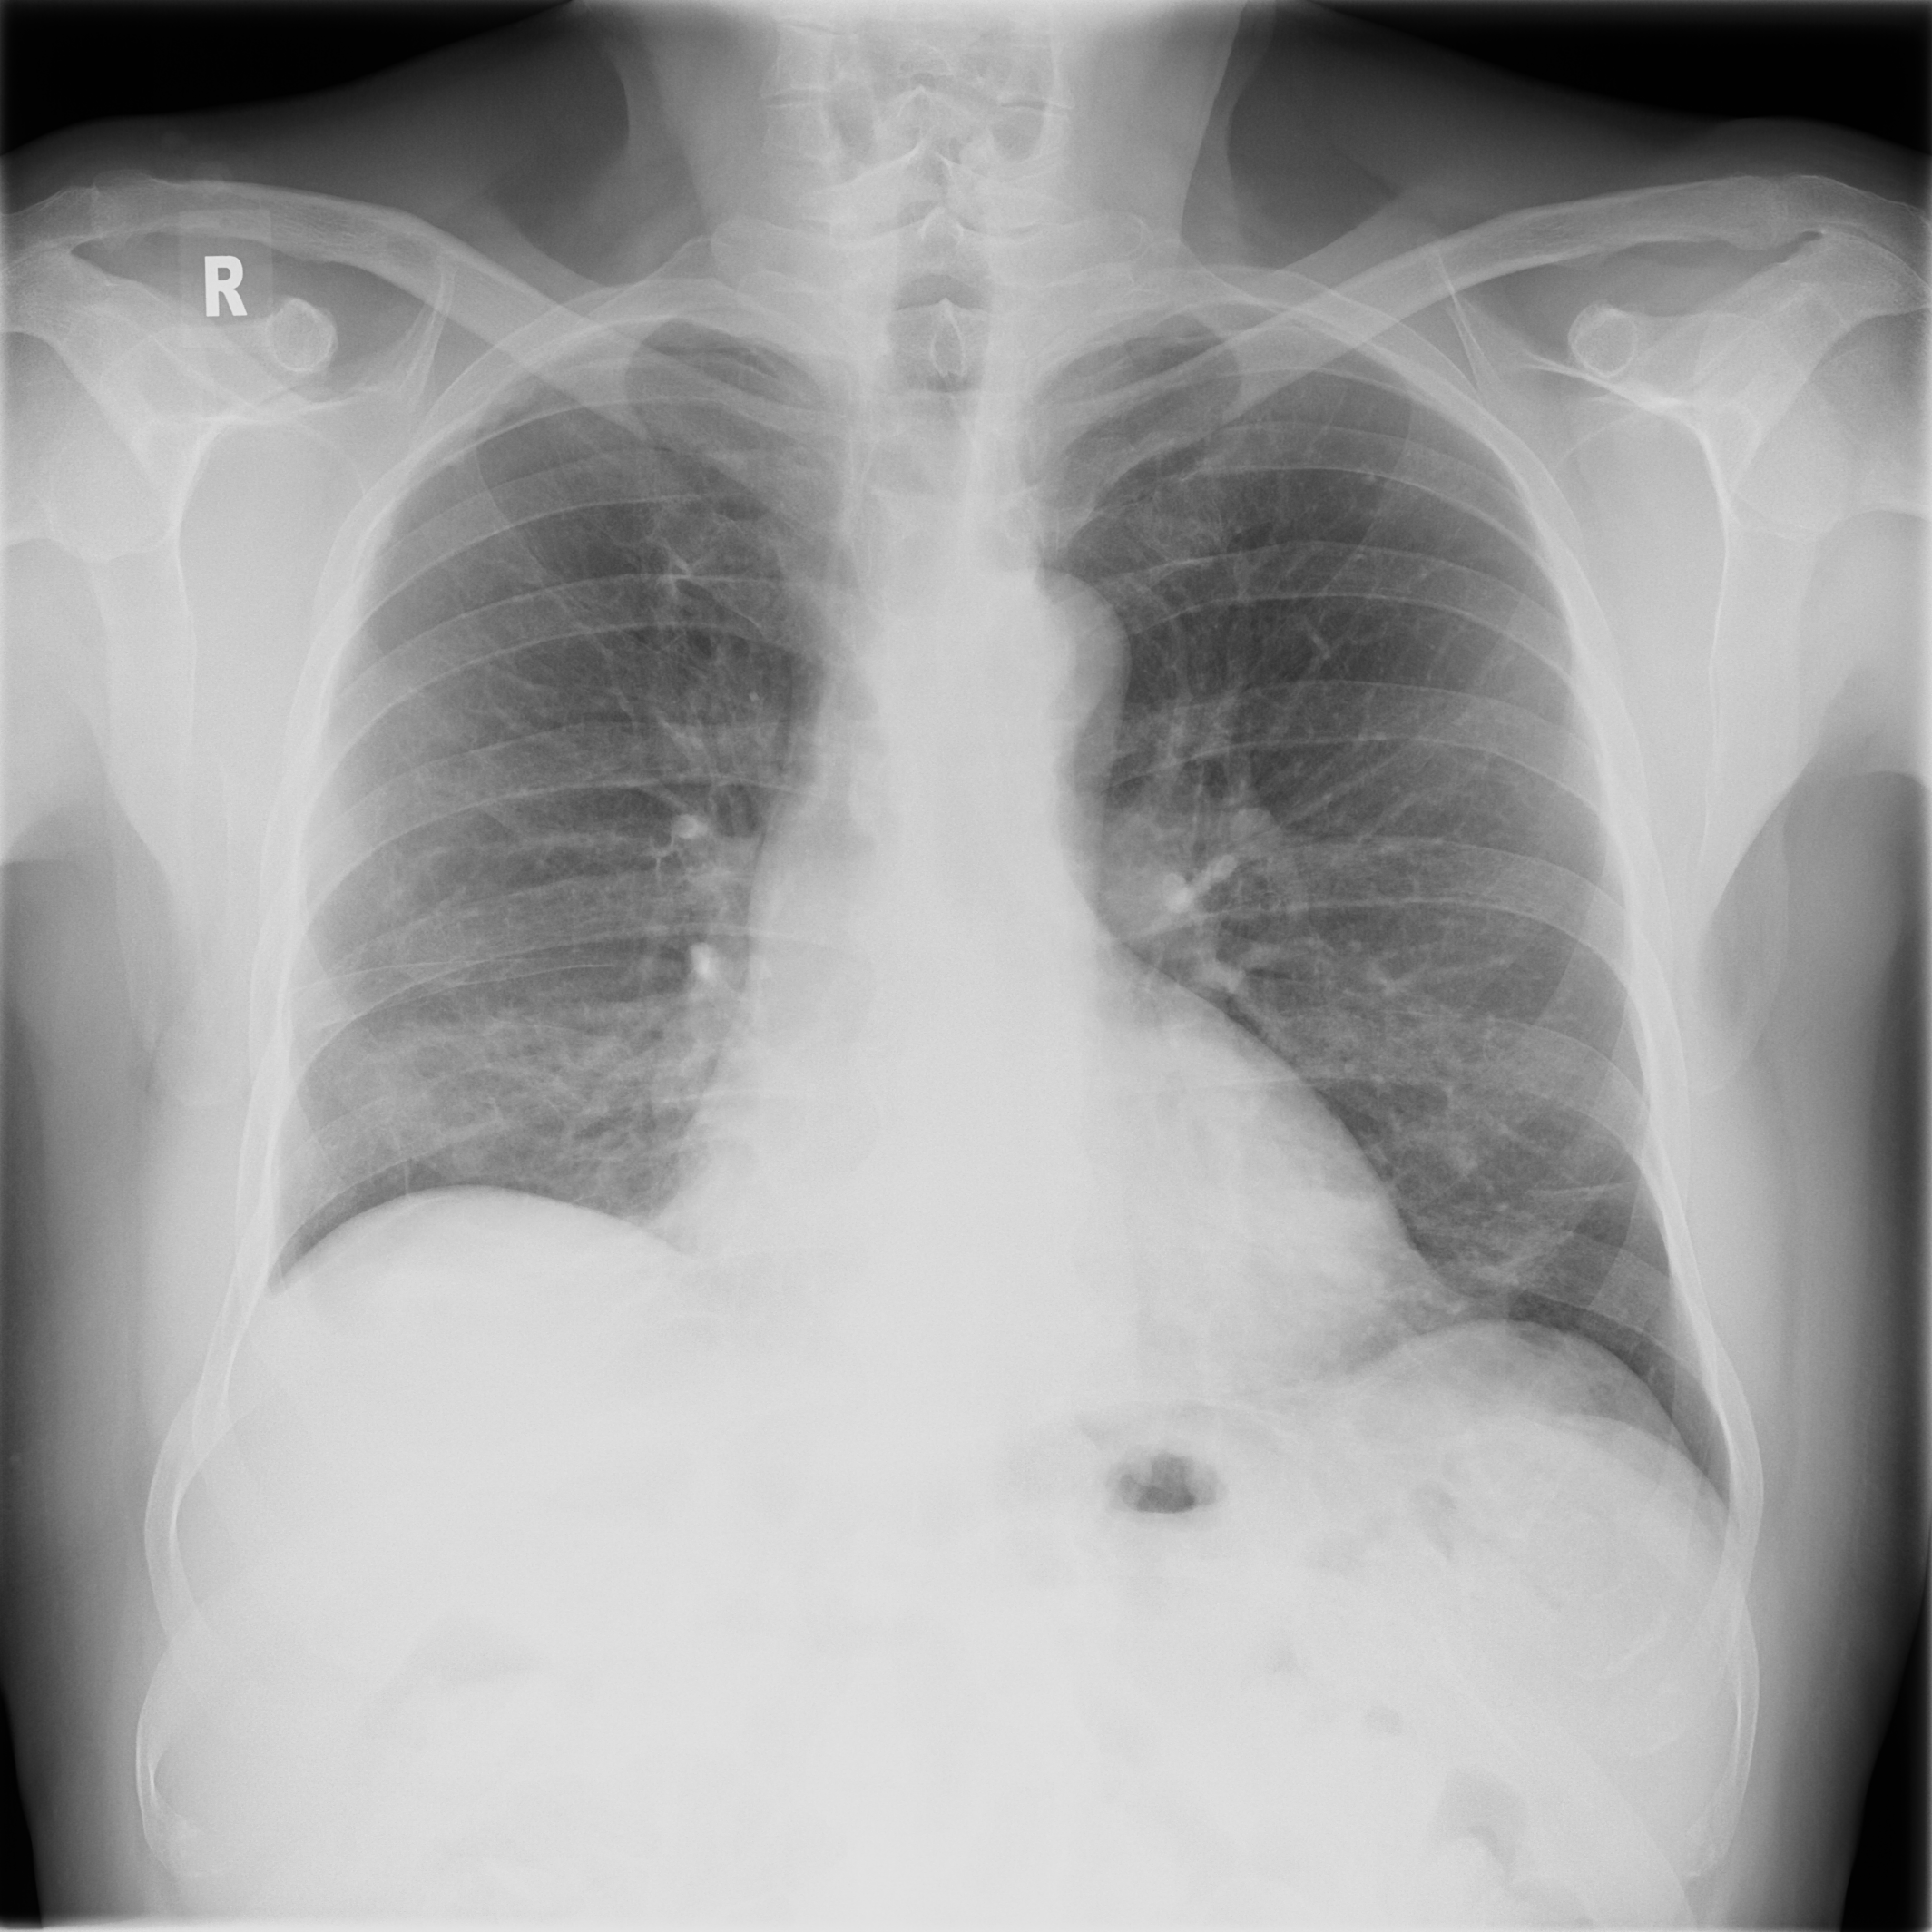

3.3 X-Ray

X-ray imaging is a fundamental form of radiography. Reducing radiation dose while maintaining image quality is a key principle in radiology known as ALARA (As Low As Reasonably Achievable) (citep \@BBN(Schiska, 2021)). New technologies and imaging techniques, such as post-processing by artificial intelligence (AI) (citep \@BBN(Harvey and Topol, 2020)), may allow diagnostic objectives to be achieved with lower radiation doses. Furthermore, advancements in X-ray have also the potential to influence and enhance Computed Tomography (CT) (citep \@BBN(Feghali et al., 2021)). Whereas CT requires complex imaging reconstruction algorithms, X-ray is more straightforward, employing post-processing for high-quality and detailed imaging, being crucial for clinical assessment of anatomical structures and potential pathologies.

3.3.1 Post-processing problem

The raw data captured during digital radiography reflects the pattern of X-ray attenuation by different tissues. The digital signal is then processed to create a greyscale image, where each shade corresponds to the radiodensity of the tissues, ranging from black for air through varying shades of grey for soft tissue and white for bone. Post-processing software refines the raw image to enhance clarity and diagnostic utility (citep \@BBN(Seeram and Seeram, 2008)). This may involve adjusting parameters such as brightness and contrast, applying filters for noise reduction, or using algorithms for edge enhancement (citep \@BBN(Krupinski et al., 2007)). The aim is to produce an image that provides the best possible diagnostic information while adhering to the ALARA principle.

Different quality properties may be desired depending on the purpose of the X-ray. For example, when visualizing the lung tissue, adjustments are made to the brightness and contrast to best highlight the anatomy and common abnormalities while minimizing noise. However, noise is less important when aiming to confirm the position of a line, tube, or foreign object. In this case, an image with edge enhancement and adjusted brightness levels may be desirable to amplify the distinction between the dense material of the object and the surrounding soft tissue.

Quality control for the provided default post-processing is usually made by the manufacturers themselves, therefore not accessible to the end user, and may be divergent to the IQ needed for clinical images (citep \@BBN(Tsalafoutas et al., 2024)). After the machine has been placed in the hospital environment, personalized post-processing settings are often determined by subjective visual inspection. Objective evaluation would help to find an optimal post-processing type for visualization, allowing faster and consistent evaluation. Beyond this setting, objective IQA is important for the development and testing of machine learning algorithms on chest X-ray images including super-resolution, denoising or inpainting methods, where PSNR and SSIM are currently the standard choice for quality assessment, see e.g. (citep \@BBN(Tran et al., 2021; Mandić et al., 2018; Wang et al., 2021; Thanh et al., 2020; Jiang et al., 2021)).

3.3.2 Data

Posteroanterior chest radiographs were acquired on two imaging systems (both Discovery XR656 HD models, GE Healthcare, USA) at Cambridge University Hospitals NHS Trust. Each scanner was being set up in the hospital with different post-processing parameters (chosen by the operating radiologists), which are used here as reference images, see Figure 7 and 8(a). Additional images, serving as real-life examples of lower quality, were produced for each radiographic exposure using multiple different post-processing settings. The post-processing was applied in the hospital directly on the scanner itself by adjusting parameters in the provided framework.

Refer to caption

(a) Reference

(b) (21.1, 0.90, 0.11)

(c) (19.5, 0.88, 0.16)

Figure 7: Chest X-Ray scans with different kinds of post-processing; (a) serves as reference and (b) is wrongly judged as better visualization by PSNR/SSIM/LPIPS.

(b) (22.8, 0.97, 0.08)

(c) (21.2, 0.96, 0.07)

Figure 8: Chest X-Ray scans with different kinds of post-processing; (a) serves as reference, (b) is wrongly judged as better visualization by PSNR and SSIM, LPIPS gives a slightly worse evaluation for (b).

FR-IQA mismatches

In Figure 7, contrast deviation and edge enhancement were reduced in (b), but increased in (c), the noise reduction algorithm was removed in both. The brightness was increased in both images but more so in (c) and low-contrast enhancement was removed in (b). The result is that (b) has relatively low contrast in the lungs compared to the reference (a) and radiograph (c). In Figure 8, edge enhancement has been dramatically increased in (b), whilst the contrast deviation and tissue contrast have been reduced. In (c), the brightness, tissue contrast and edge enhancement have been slightly increased. Consequently, (b) provides low contrast in the lungs with excessively prominent lung markings and vasculature which make it harder to detect abnormalities such as a pneumonia.

All of the chosen FR-IQA metrics wrongly judge (b) as the better image in the first example Figure 7, and the results in (b) and (c) of the second example Figure 8 are quite close, where PSNR and SSIM are also providing the wrong order. The tested measures are not suitable to evaluate the quality of data sets with X-Ray images that have large variations regarding contrast, luminance and sharpness.